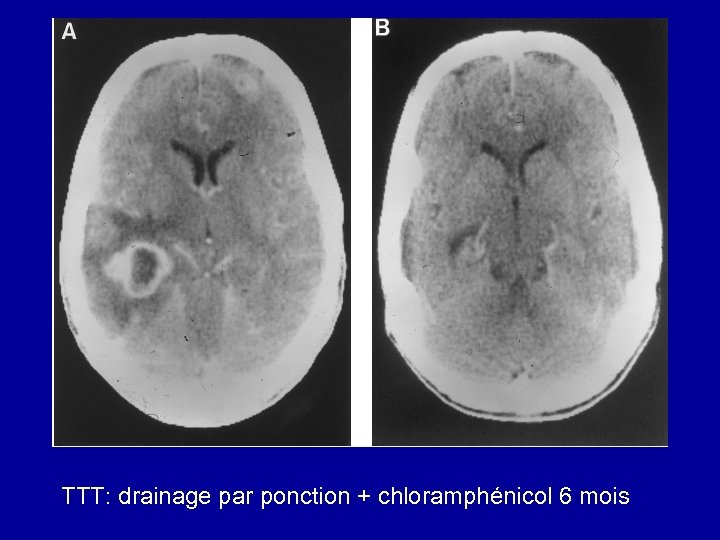

TTT: drainage par ponction + chloramphénicol 6 mois